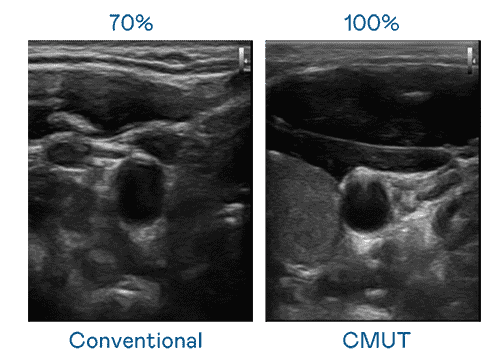

CMUT 技术是一种用电容式微机电元件来产生超音波讯号的技术。。与传统 PZT 压电式技术相比,,,CMUT 频宽增加 30%,,更宽频的超音波讯号让影像解析度大幅提升,,是实现高影像品质医疗超音波扫描、、、促进精准医疗发展的关键技术。。。

大频宽带来超清晰影像

超音波影像的解析度高低,,,,首先取决于探头能发出的讯号频宽。。尊龙z6 CMUT 可提供高清晰的超音波讯号,,提供高频宽、、、高灵敏度、、影像纹理细节更高的超音波影像,,,,协助医护人员缩短影像判读时间及利用精准的医疗影像进行诊断。。